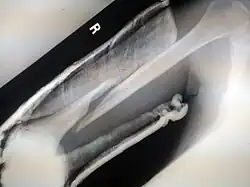

- Spiral fracture – a fracture where at least one part of the bone has been twisted

Spiral fracture or torsion fracture | At least one part of the bone has been twisted (image shows an arm-wrestler) | Torsion on the bone[37] | May rotate, and must be reduced to heal properly |